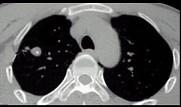

问题 男性,25岁,低热、咳嗽2个月。胸部CT见图,最可能的诊断是 ( )

选项 A.急性血行播散型肺结核 B.肺结核球 C.肺癌 D.肺脓肿 E.支气管扩张

答案 B